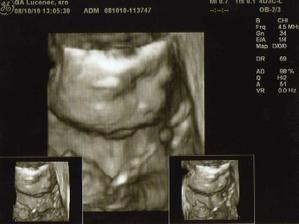

Nase 3D sono